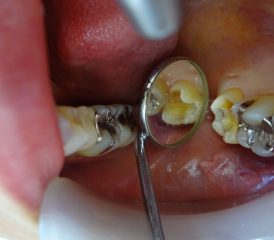

左上の奥歯に詰めてあった銀の詰め物が外れてしまい、内側が虫歯になっていました。

保険の銀の詰め物は金属製で丈夫な素材ですが、長い間使用していることによる変形や接着に使用したセメントが少しずつ溶け出し、経年劣化が発生します。

そうなると、時間が経過した詰め物と歯の間には小さな隙間ができ、そこから細菌が入り込んで虫歯ができてしまうこともあります。